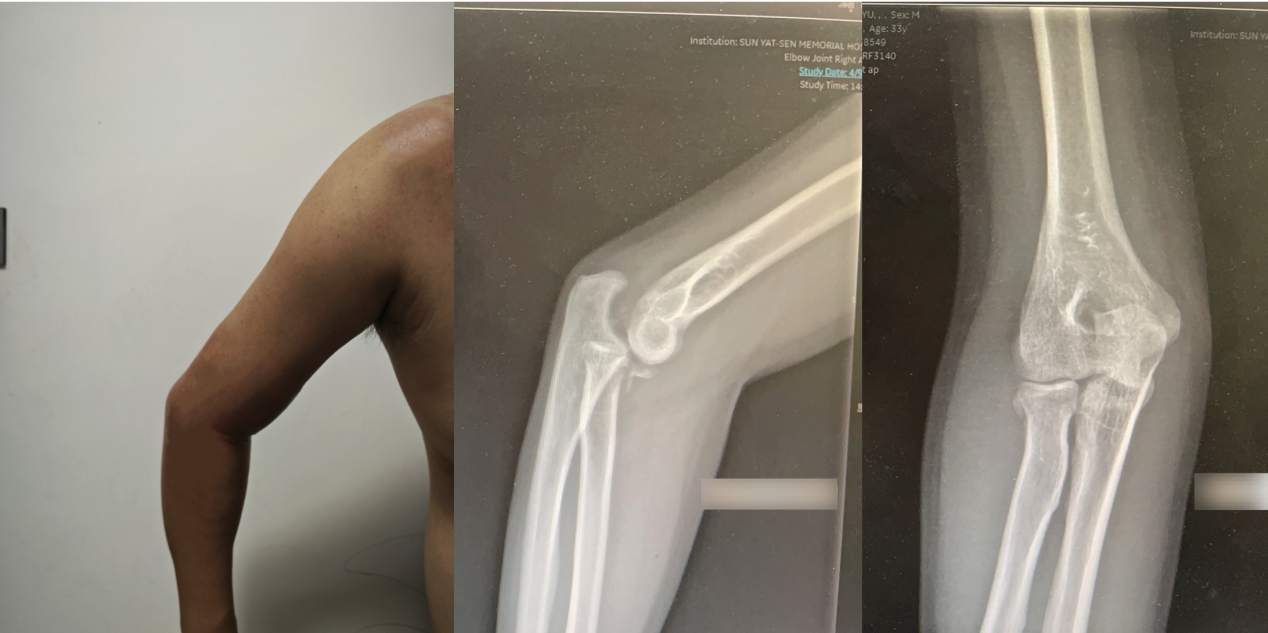

当他来到中山大学孙逸仙纪念医院运动医学科时,检查结果令人心惊:右肘关节已处于固定性后脱位状态,同时合并两处关键骨折(桡骨小头和尺骨冠突骨折),肘关节解剖结构明显紊乱,关节僵硬性严重受损。陈仲副教授指出,这已从急性“肘关节恐怖三联征”拖成了更棘手的“陈旧性”损伤,并叠加了严重僵硬,治疗难度倍增。

林先生右侧肘关节呈僵硬状态,活动受限。X线检查显示其肘关节处于后脱位,并伴有桡骨头及尺骨冠突骨折

肘关节恐怖三联征是在肘关节脱位发生多发韧带损伤的基础上出现了“桡骨头及尺骨冠突的骨折”